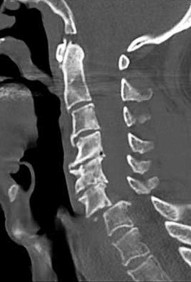

An 82-year-old male with severe chronic obstructive pulmonary disease and heart failure presents after a mechanical fall from a standing height. He reports significant neck pain. Neurologic examination is unremarkable.

Imaging demonstrates a displaced Type II odontoid fracture. What is the most appropriate management for this patient?